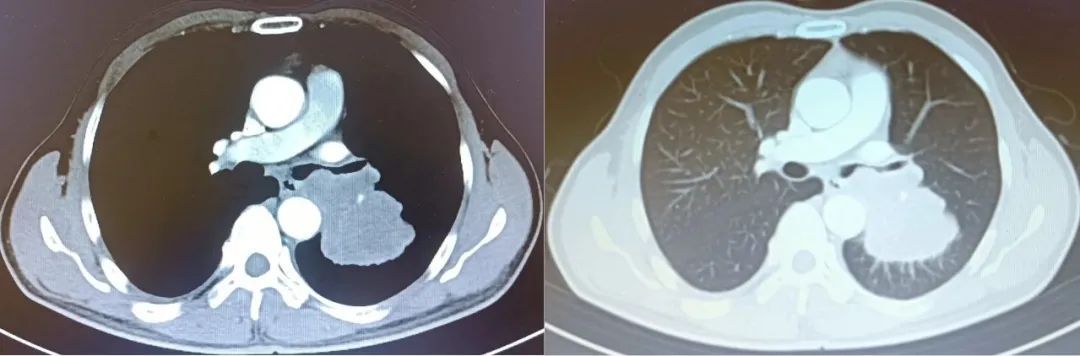

陈大哥突发咳嗽、咳痰有一个月的时间,一开始没有重视,直到近期出现呼吸困难,严重影响了日常生活。于是,陈大哥在家人的陪同下,来到了漳州第三医院呼吸与危重症医学科门诊就诊。经过胸部CT检查,陈大哥的气道已堵塞严重,并存在肺部支气管截断等情况。

▲CT检查影像